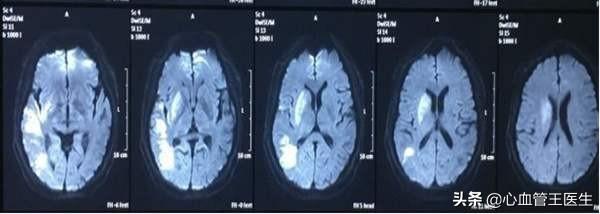

CTスキャンで「脳梗塞」が見つかった。発見と同時に来院して検査・治療を受けたが、血栓溶解療法に最適な「黄金の6時間」を逃し、抗血小板・抗凝固療法、脳保護、脳循環改善などの対症的支持療法による保存的治療しかできなかった。

実際、脳梗塞の初期症状は一様ではなく、脳梗塞の部位が異なれば、梗塞の部位も異なり、管理する機能部位も異なるため、体のさまざまな部位で閉塞が生じ、機能に影響を与え、その結果、症状も異なる。

上記の顔面の非対称性、口角の曲がり、手足の力の非対称性、不明瞭または失語症に加え、脳梗塞は片麻痺、頭痛、嘔吐、昏睡、両眼半盲、めまい、眼振、複視、四肢麻痺、昏睡、脳死を引き起こすこともある。

1.脳梗塞と脳出血

脳梗塞と脳出血の症状は基本的に同じであるため、上記のような症状が出たときに、それが脳出血なのか脳梗塞なのかを正確に判断することは難しい。脳出血か脳梗塞かは、病院に行って脳CTを撮って初めて正確に判断できます。